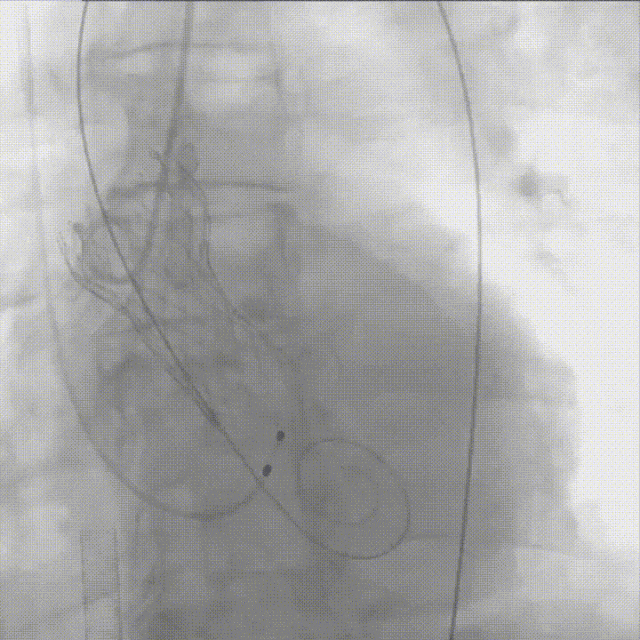

快速起搏下瓣膜初次释放至极限回收位;

瓣膜初次释放

造影评估瓣膜位置满意,遂完全释放瓣膜;

瓣膜初次释放后造影评估

瓣膜完全释放